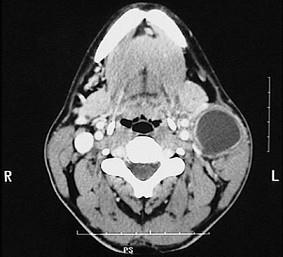

问题 40岁女性,右上颈部包块发现5年,增长不明显。近3天发生上呼吸道感染,肿物突然增大,伴疼痛。检查见肿物位于胸锁乳突肌上1/3前缘,质软,有波动感,无搏动,体位试验阴性。CT?检查如图。最可能的诊断是()

选项 A.海绵状血管瘤 B.神经鞘瘤 C.囊性水瘤 D.鳃裂囊肿 E.甲状舌管囊肿

答案 D